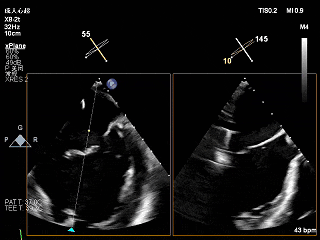

全麻下穿刺右股静脉,在TEE指导下完成房间隔穿刺,穿刺处与二尖瓣瓣环距离3.85cm。将superstiff导丝送至左房,应用18F鞘管扩张穿刺部位,沿导丝将可操控导引导管送入左肺静脉。

将“大鞘”送入左房

3D下大鞘的穿刺位置大概在3点钟方向

左房较大,完成骑跨

“+M”使夹子垂直于瓣环平面

“弹”道测试

打开夹子,调整轴向

3D上彩确认夹子位置

2维上彩确认夹子位置

夹子关小进入左心室